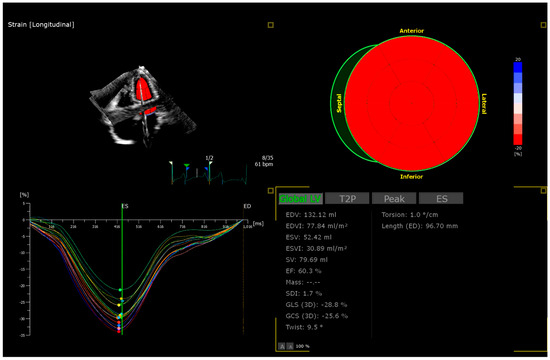

Impact of Acute Lymphoblastic Leukemia Treatment on Left Ventricular Function Assessed in 2D and 3D Speckle Tracing Echocardiography—Preliminary Results

by Julia Haponiuk-Skwarlińska, Halszka Kamińska, Katarzyna Albrecht, Paweł Łaguna and Bożena Werner

J. Clin. Med. 2025, 14(24), 8682; https://doi.org/10.3390/jcm14248682 - 8 Dec 2025

Background/Objectives: Acute lymphoblastic leukemia (ALL) is the most common childhood malignancy with promising survival. ALL treatment involves the use of cardiotoxic anthracyclines. The data for children on new methods of echocardiographic detection of early-onset anthracycline-related left ventricle dysfunction is lacking. Methods: [...] Read more.

Background/Objectives: Acute lymphoblastic leukemia (ALL) is the most common childhood malignancy with promising survival. ALL treatment involves the use of cardiotoxic anthracyclines. The data for children on new methods of echocardiographic detection of early-onset anthracycline-related left ventricle dysfunction is lacking. Methods: Consecutive children with ALL were prospectively enrolled. The echocardiography was performed after ALL diagnosis and before initiation of anthracyclines (first assessment) and after induction and intensification therapy completion (second assessment). The left ventricle echocardiographic assessment involved conventional two-dimensional (2D) echocardiography, 2D speckle tracing, and three-dimensional (3D) echocardiography with offline analysis for 3D speckle tracing. Results: The preliminary group of 32 children presented with mean time between the first and second assessment of 7.3 ± 1.5 months (min.5.3–max.11.4). All children were treated by the same treatment protocol and received doxorubicin and daunorubicin. The mean cumulative equivalent anthracycline dose was 165.6 ± 54.0 mg/m2. Statistically significant differences between the first and the second echocardiography were observed in LV-GLS-2D −24.6 ± 3.3% vs. −21.0 ± 3.3%; p < 0.001, LVEF-3D 59.7 ± 7.3% vs. 55.1 ± 3.0%; p = 0.010, LV-GLS-3D −23.3 ± 5.3% vs. −20.4 ± 2.8%; p = 0.031 and LV-GCS-3D −26.3 ± 5.9% vs. −21.9 ± 3.2%; p = 0.017. The differences in LVEF-2D and LV-GRS-3D were not statistically significant. The decrease of >15% from the first assessment was observed in 9 (28%) in LV-GLS-2D, 8 (25%) in LV-GLS-3D, 11 (34%) in LV-GCS-3D and only in 4 (13%) patients in LV-GRS-3D. Conclusions: Two-dimensional and three-dimensional speckle tracing and 3D-LVEF may be sensitive indicators of subclinical left ventricular function impairment in children treated for ALL with anthracyclines. However, this is a preliminary analysis of the planned cohort; our results should be interpreted with caution. Full article

Show Figures

Figure 1